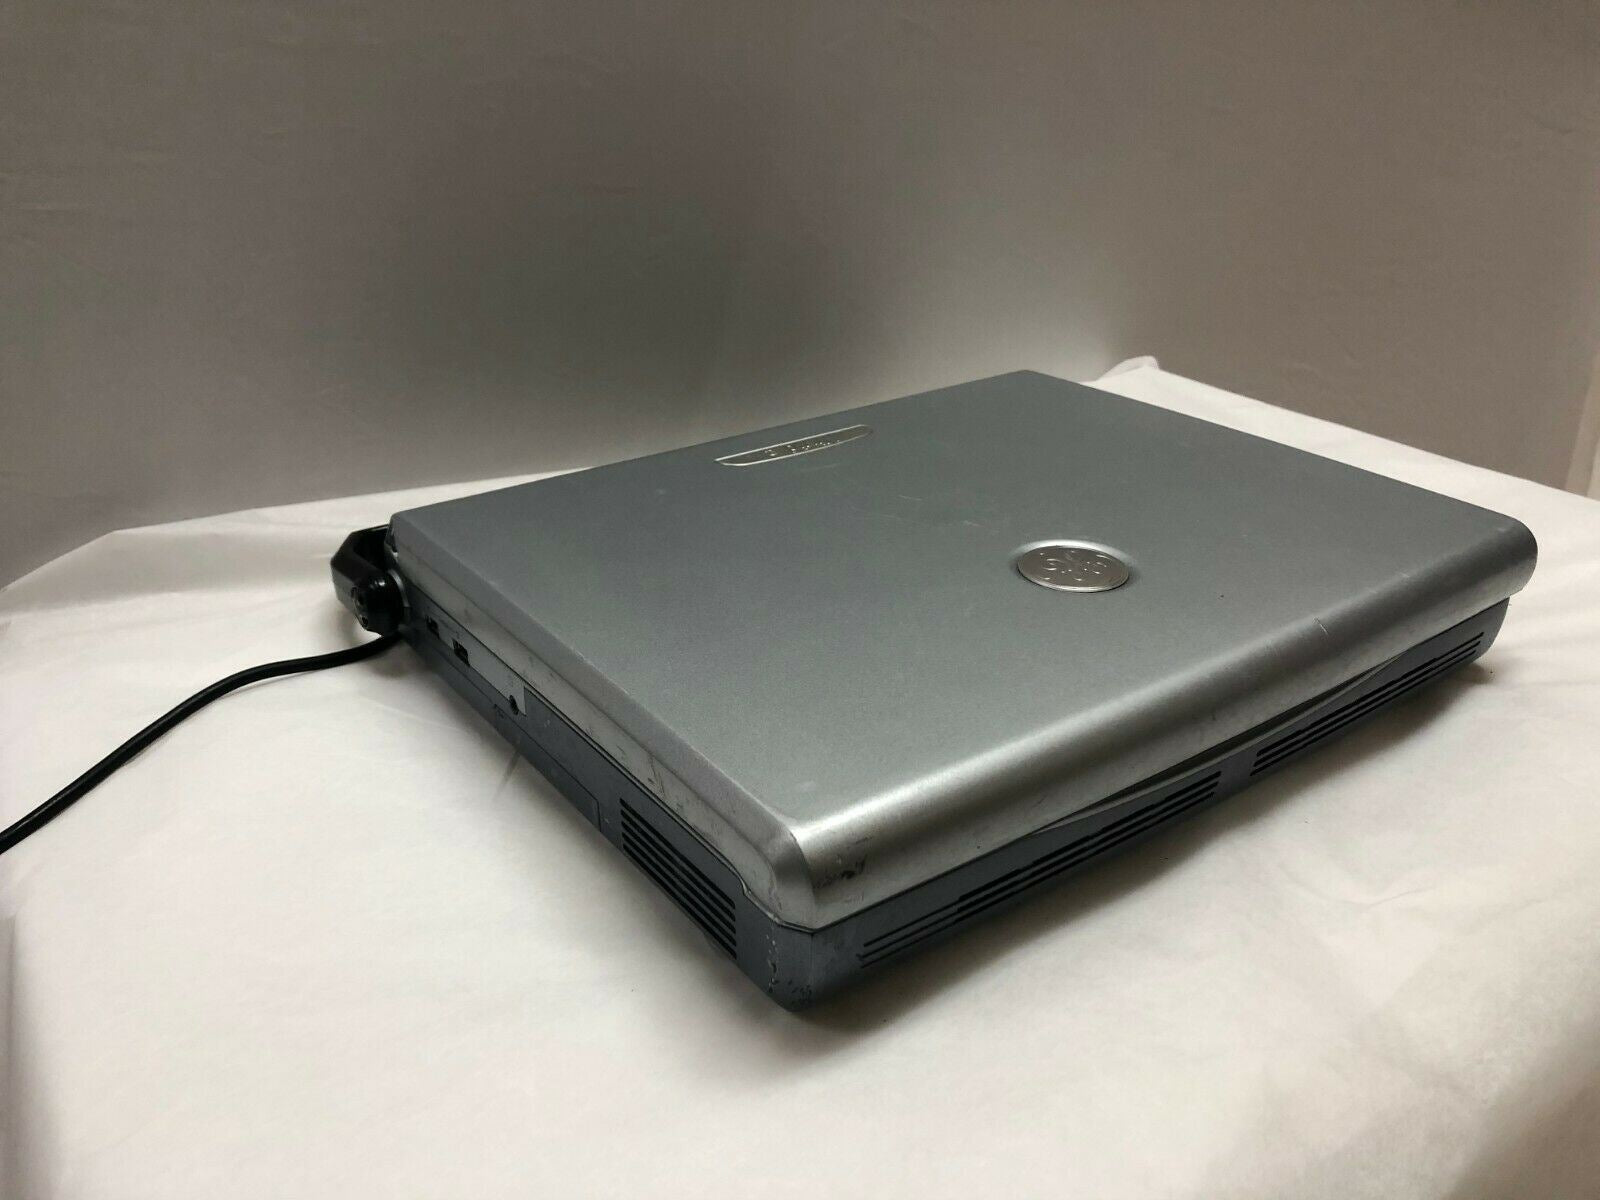

GE Vivid E Color Doppler Ultrasound Scanner, CW Two probes Cardiac and Linear

PHILIPS CX50 PORTABLE ULTRASOUND MACHINE DOM: 2011 WITH CART

GE Vivid E Color Doppler Ultrasound Scanner, CW Two probes Cardiac&Linear 2010